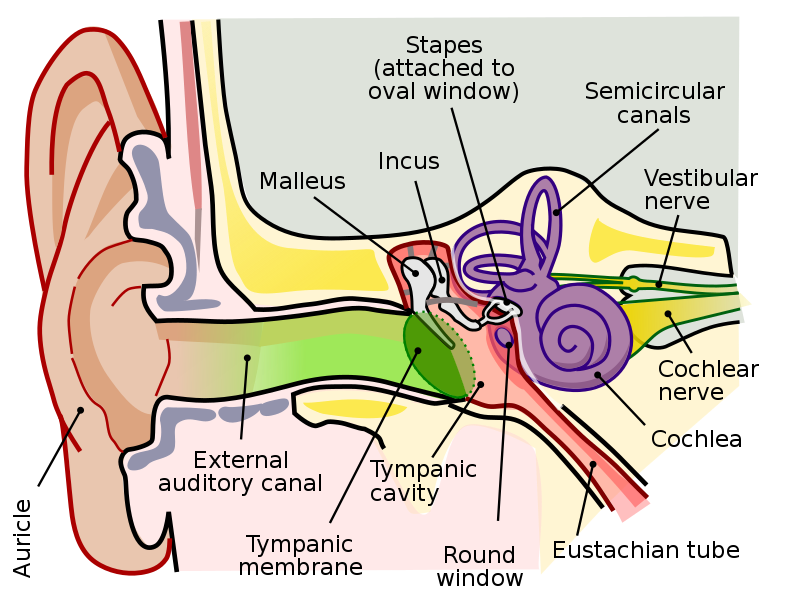

CN VIII

- Vestibular n. (平衡)

- Cochlear n. (聽力)

CN IX

- Tympanic n.

- 中耳、鼓膜內面、耳咽管(Eustachian)

Temporal bone

- Carotid canal

- Ext. acoustic meatus

- Int. acoustic meatus

- CN VII, VIII

- Jugular foramen

- int. jugular v.

- CN IX, X, XI

- Stylomastoid foramen

- Petrotympanic fissure

Ear

Sensor:CN V

- Opening of Pharyngotympanic tube (auditory tube, Eustachian tube)

Pharyngotympanic tube

- 通過 Temporal bone

- 後2/3是軟骨

- 通過 Temporal bone

- 後2/3是軟骨